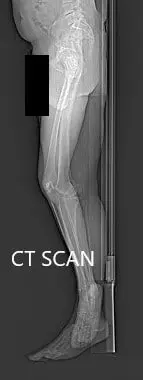

Se discutieron extensamente los riesgos, beneficios y alternativas. Se consideró candidata para una prótesis de rodilla personalizada. El paciente estuvo de acuerdo con el plan. Unas semanas antes se realizó una tomografía computarizada de las extremidades inferiores del paciente. La planificación precisa de los cortes y desplazamientos óseos fue posible gracias a los datos de la tomografía computarizada.

Imágenes topológicas de tomografía computarizada preoperatoria.